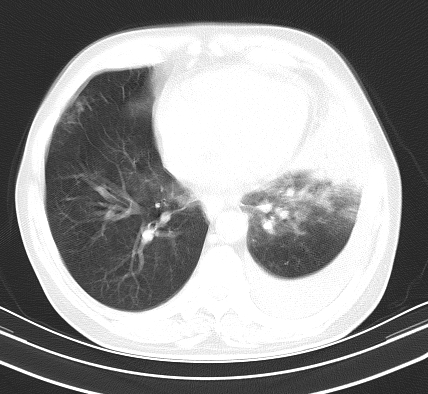

以下是引用老爱克斯新网客在2008-7-31 6:30:00的发言:[br]左肺上叶大片状病灶,左肺上叶支气管狭窄呈鼠尾状,左肺门增大,纵隔内见肿大淋巴结,左侧胸腔积液,余肺清晰。左肺中心型肺癌淋巴结转移,

以下是引用zjb在2008-7-31 6:32:00的发言:[br]左侧中心性肺癌 阻塞性肺炎 肺不张 胸腔积液 建议气管镜

以下是引用zjzjr在2008-7-31 8:45:00的发言:[br]考虑左侧中心性肺癌伴阻塞性肺炎,左肺上叶肺不张,纵隔淋巴结转移;左侧胸腔积液。建议行纤支镜检查。

以下是引用sdzyy在2008-7-31 8:47:00的发言:[br]病灶较治疗前有所进展,胸水增多, 左侧中心性肺癌 并 阻塞性肺炎 肺不张 胸腔积液 可能性大; 建议气管镜检查。 [br] [br]